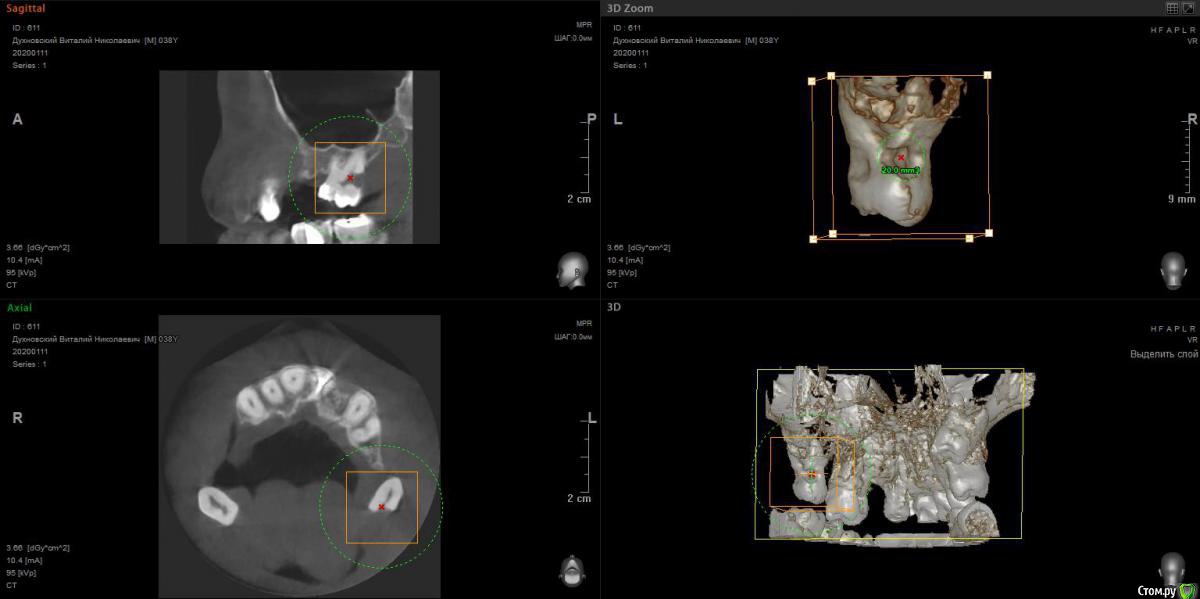

Просьба ко всем не равнодушным! Глянуть КТ верхней челюсти, 27 зуб  и место где удалили 16, может ещё где-то могут быть проблемы.  На фото видно где покраснение на дёснах, в этих местах возникают боли при движении головой. Бывает боль слева если засыпаю на левой стороне. Набуханий или флюсов нигде не видно.Прошу делиться мнениями, для меня это очень - очень важно. Стоматолог визуальных проблем на месте удалённого зуба не видит, всё зажило.

По данным КТ в зоне удалённого зуба 16 ничего особенного, разве что, ретенированный (непрорезавшийся) зуб 18.

Зуб 27 требует внимания, необходим очный осмотр.

Также стоит обратить внимание на зубы 21 и 24